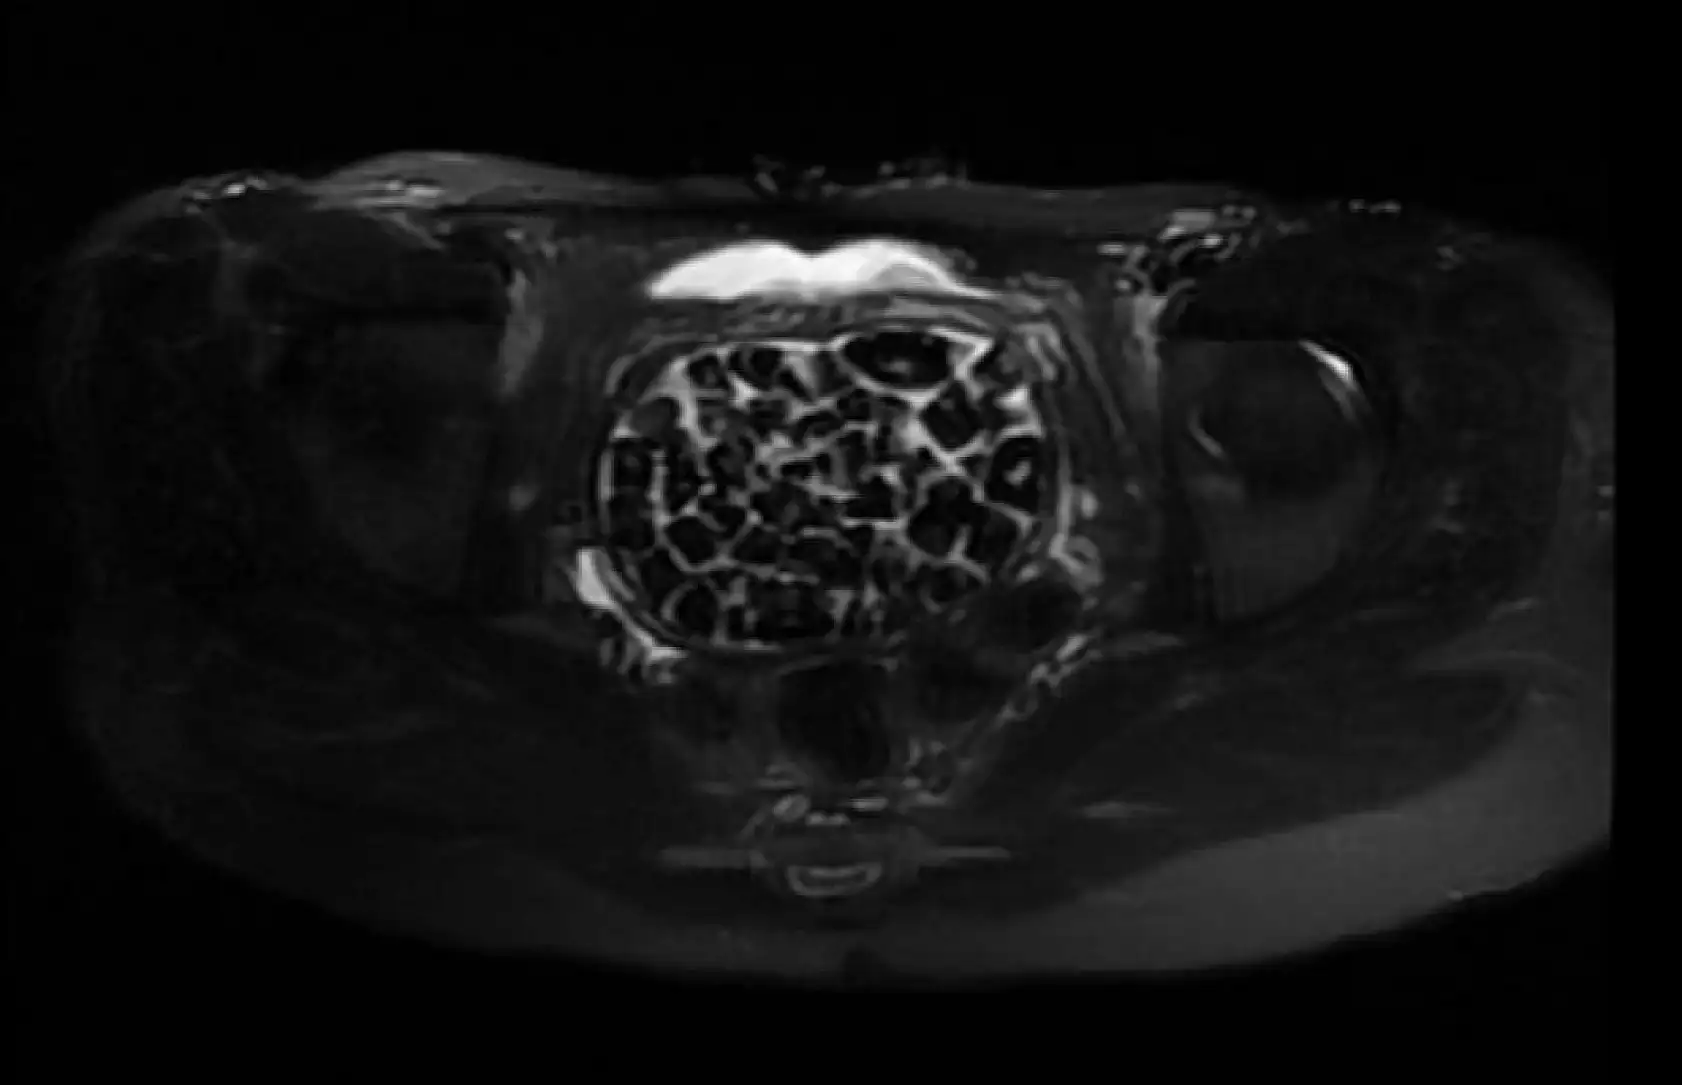

Doğumsal ürolojik hastalıkla dünyaya gelen 21 yaşındaki Fatma Nur Öztürk, şiddetli karın ağrısı şikayetiyle hastaneye gitti, yapılan operasyonla vücudundan 287 adet taş çıkarıldı. Taşlar hem sağlık ekibini hem hasta ve ailesini şok ederken uzmanlar, 'Mesaneden vajene geçtiğimiz esnada tüm vajenin taşlarla dolu olduğunu gördük. Biz de o kadar taş beklemiyorduk, çok şaşırdık, en büyüğü 2,5 santim boyutlarında olan irili ufaklı 287 taş. Literatürde çok nadir görülen bir olay' derken hasta Öztürk, 'Ağlatacak dereceye getiren ağrılardı. 287 taş denince çok şaşırdık, çakıl taşı resmen. Şu an kendimi çok iyi hissediyorum' dedi.

Genç kızın uzun süredir devam eden karın ağrısı olduğunu söyleyerek sözlerine başlayan Jinekolojik Onkoloji Uzmanı Op. Dr. Emin Erhan Dönmez, "Mesane taşları olduğu düşünülerek daha büyük bir hastaneye refere edilmiş. Aramızda mini bir konsey yaparak muayene ettik. Vajen bir hazne görevi görerek orada durağan bir idrar, uzun süre beklediği için idrar içindeki minerallerde çökerek taşlar oluşmuş. Mesanedeki idrarın vajene akmış olabileceği ve vajende göllenen idrar nedeniyle taşların burada oluşacağını düşündük, ameliyatımızı planladık. Ameliyata tanı amaçlı girmiştik, sistoskopi (Mesane gibi idrar yollarını kapsayan kısımlardaki rahatsızlıkların teşhis ve tedavisinde kullanılan endoskopik bir yöntem) dediğimiz ameliyatı Erkan Hocam ile birlikte gerçekleştirdik. Önce mesaneyi bir görüntüledik, mesane tabanına yaklaşık 2-3 cm’lik bir alandan vajene fistülize olduğunu gördük. Mesaneden vajene geçtiğimiz esnada tüm vajenin taşlarla dolu olduğunu gördük. Tanı amacıyla girdiğimiz ameliyatta her şey de olağan gittiği için tedaviye geçtik. Taşların çıkabileceği kadar bir genişlik sağladık. Daha sonra yaklaşık en büyüğü 2,5 cm boyutlarında olan, irili ufaklı 287 tane taşı ameliyat esnasında çıkarmış olduk. Taşların tekrarlamaması için idrarın göllenmemesi, en azından dışarıya rahatça boşalabilmesi için vajinal rekonstrüksiyonu sağladık. Ameliyatta da herhangi bir problem yaşamadık. Literatürü Erkan Hocam ile birlikte değerlendirmiştik. Primer olarak vajende birikmiş olan bu kadar çok sayıda taşla ilgili bir makale görmedik, rastlamadık" dedi.